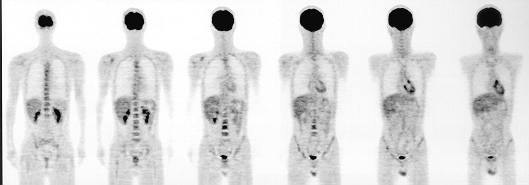

1981’(S.56) リング式カメラとポジトロンカメラ

秋田脳研と共同開発(ハイブリッド)

空間分解能: 9.6mm FWHM(高分解能モード、視野中心)

3リング(スライス)方式

1号機はNaI(Tl)を採用しシングルホトンとポジトロンの撮影可能なハイブリッドタイプとした。

BGO検出器のポジトロン専用装置